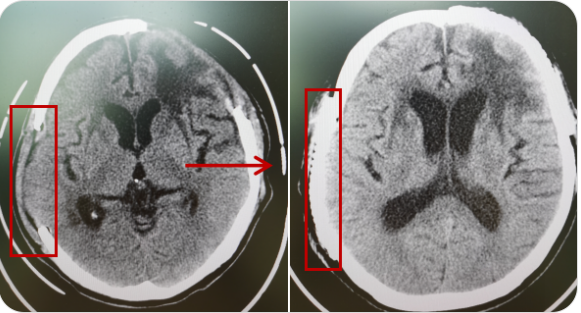

精通颅内动脉瘤介入栓塞和手术夹闭双技术,系统掌握脑动静脉畸形、颈内动脉海绵窦漏、硬脑膜动静脉漏等颅内血管疾病的诊疗和手术,精通颈动脉、椎动脉狭窄的血管内重建技术,以及颈动脉狭窄的内膜剥脱手术技术。在颅内肿瘤、椎管内肿瘤、颅脑损伤、高血压脑出血等疾病的诊治和手术,脑功能性疾病立体定向手术治疗等方面也积累了丰富的经验。